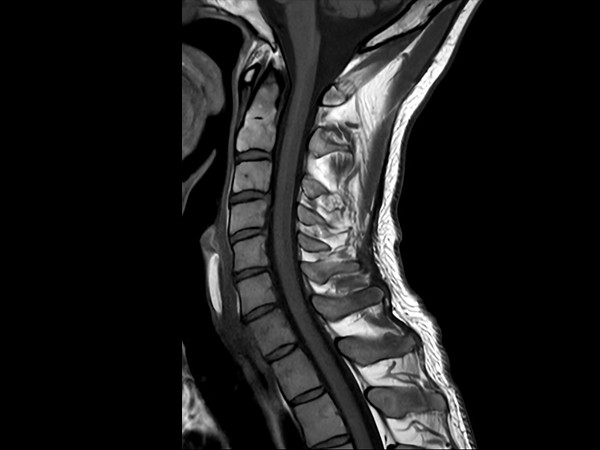

High quality Cervical Spine imaging with SmartSpeed Precise